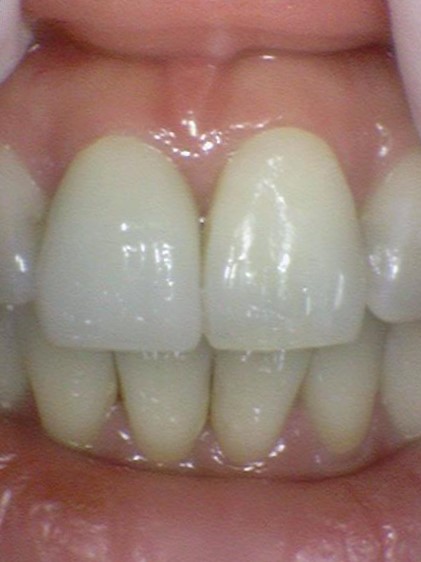

심미성과 강도를 모두 갖춘 소재를 사용한 지르코니아 크라운.

오래전 사용하던 골드크라운처럼 금색이 아니라 하얀 색이므로 티가 나지 않습니다.

앞니 중에 어떤게 지르코니아 크라운인지 티가 나시나요? ↓

앞니 중에 어떤게 지르코니아 크라운인지 티가 나시나요?